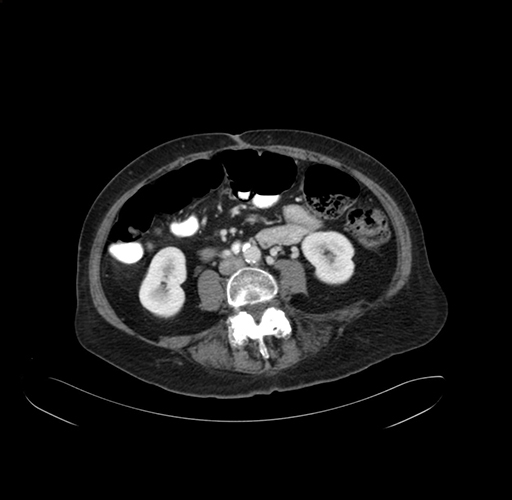

Pre-Chemo: Axial Venous

Axial Venous